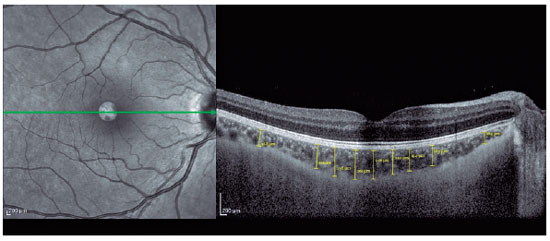

SD-OCT (Spectralis; Heidelberg Engineering, Heidelberg, Germany) was used to visualize the RNFL and choroid. The scan quality ranged from 0 (no signal) to 40 (excellent), and only high-quality images (images with a centered and well-focused optic disc with a signal strength of >20 Db) were selected. The EDI mode was used to improve choroid visualization. Choroidal measurements were performed by two independent experienced physicians who were blinded to the patients. Examinations were performed between 9:00 and 11:00 AM to avoid diurnal variations(11). The right eye values were used for statistical analyses. RNFL thickness was determined using an optic nerve head scan. A volumetric scanning protocol was used to visualize a 15 × 15 region surrounding the optic nerve head (circle scan size: 3.4 mm). The average thicknesses of RNFL and four quadrants (superior, nasal, inferior, and temporal; 90° each) were automatically measured using SD-OCT in the peripapillary area (Figure 1). Choroidal thickness was defined as the distance between the outer retinal pigment epithelial line and the hyperreflective line behind the large choroidal vessel layer at the scleral interface. The thickness was measured manually at 17 different points: at the foveal center and 0.5, 1, 1.5, and 3 mm from the foveal center within the nasal, temporal, inferior, and superior quadrants (Figure 2). Box plots of the OCT measurements for the AN and control groups are shown in figure 3.

The study included 30 patients with AN (26 females and 4 males) and 30 healthy adolescents (23 females and 7 males). The average disease duration in the AN Group was 11.1 ± 9.2 months. The mean age in the AN and Control groups was 15.0 ± 1.6 years and 15.3 ± 1.6 years, respectively. The mean BMI in the Control Group was 22.8 ± 1.6. The demographic and disease characteristics of the participants are summarized in table 1. A comparison of the right eye measurements between the two groups is presented in table 2. The temporal (77.8 ± 11.4 μm vs. 87.5 ± 13.7 μm ) and inferior (132.6 ± 16.1 μm vs. 149.4 ± 15.3 μm) RNFL thicknesses were significantly lesser in the AN Group than in the Control Group (p<0.05). The choroidal thickness in all temporal and inferior regions (0.5, 1.0, 1.5, and 3.0 mm from the fovea) was significantly lesser in the AN Group than in the Control Group (p<0.05). The choroidal thicknesses in the nasal regions 1.0, 1.5, and 3.0 mm from the fovea were also statistically lesser in the AN Group than in the Control Group (p<0.05). In the superior region, the choroidal thickness 0.5 mm from the fovea was significantly lesser in the AN Group than in the Control Group (p<0.05). The central macular (247.6 ± 26.0 μm vs. 266.6 ± 19.5 μm ) and subfoveal (311.8 ± 34.7 μm vs. 337.0 ± 38.2 μm) choroidal thicknesses were significantly lesser in the AN Group than in the Control Group (p<0.05). Our analysis did not reveal a significant correlation between any OCT parameter and the patients' BMI (p>0.05). However, as the disease duration increased, the RNFL thickness in the inferior region significantly decreased (p<0.05). Subgroup analysis revealed no significant difference in any variable between the restrictive and binge-purge AN types. The best-corrected visual acuity was 6/6 in all eyes.